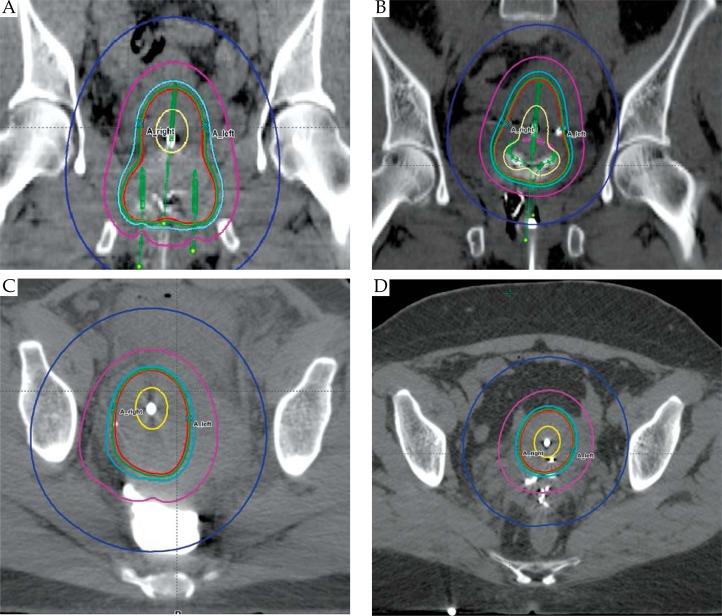

Following pelvic external beam radiation therapy (EBRT), a total of 52 computed tomography-based plans from 13 patients with cervical cancer (FIGO IB2-IIIB) were evaluated for HDR brachytherapy. Prescription was 7 Gy to the ICRU point A for four weekly fractions. Gastrointestinal and genitourinary toxicities were evaluated. Clinical target volume (CTV) and organs at risk were delineated on CT scans. Bladder, rectum, and sigmoid mean doses and D2cc were calculated. Treatment time and irradiated tissue volume were compared. Percent of CTV receiving 100% (CTV100%) of the prescribed dose as well as the percent of the prescription dose covering 90% of the CTV (D90) were evaluated.

Gastrointestinal and genitourinary toxicities were not different between TO and TR applicators. No significant differences in the dose to the right and left point A, or the left point B were observed. TO delivered a higher dose to right point B. Organs at risk doses were similar between the two applicators, except mean rectal dose was lower for TO applicator. Overall, TO treats a larger tissue volume than TR. Mean treatment time was shorter for TR. Tumor coverage (D90 and CTV100%) was equivalent between TO and TR applicators.